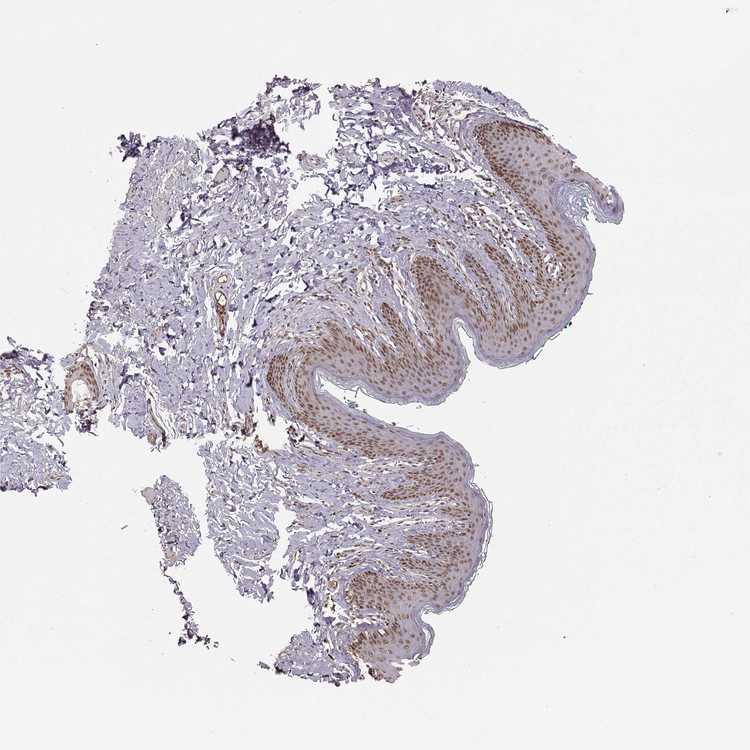

SKIN 1 - Antibody stainingi

Antibody staining in the annotated cell types in the current human tissue is reported as not detected, low, medium, or high, based on conventional immunohistochemistry profiling in selected tissues. This score is based on the combination of the staining intensity and fraction of stained cells.

Each image is clickable and will lead to virtual microscopy that enables deeper exploration of all samples and also displays staining intensity scores, fraction scores and subcellular localization as well as patient and tissue information for each sample.

Antibody HPA069022

Langerhans Medium

Fibroblasts Medium

Keratinocytes Medium

Melanocytes Medium